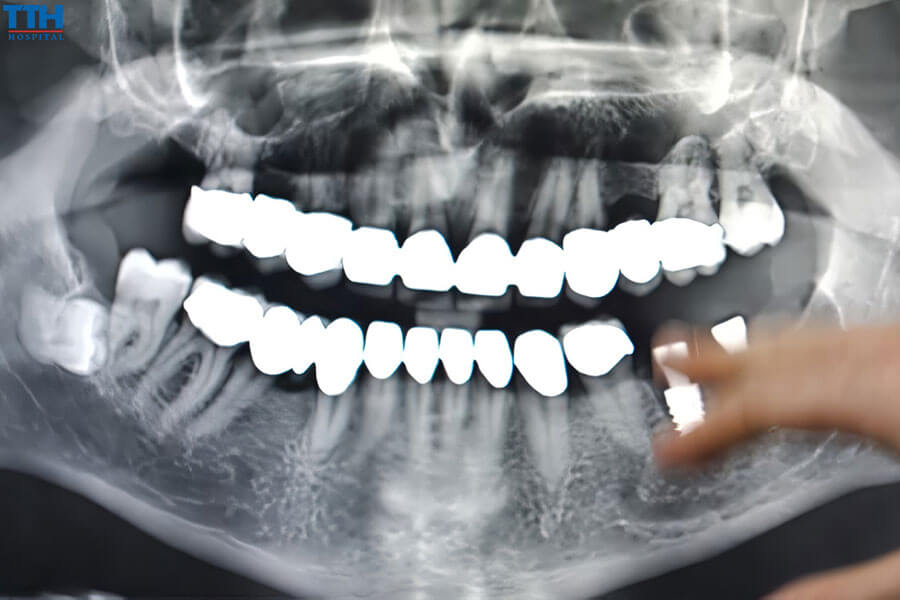

3.1. Các phương pháp đánh giá

- Chụp X-quang thông thường

- Chụp CT 3D (Cone Beam CT)

- Đánh giá mật độ xương

- Chụp X-quang và CT 3D